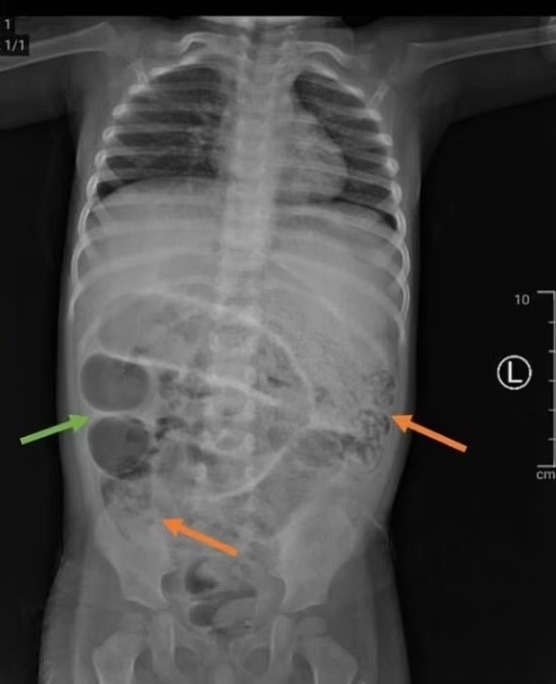

وبحسب صحيفة ديلي ميل، فقد بدأت أعراض الطفل كحالة إمساك عادية، إلا أن حالته تدهورت سريعًا بعدما بدأ يتقيأ ديدانًا في اليوم التالي. دفعت الأشعة السينية الفريق الطبي للاشتباه بوجود انسداد حاد في الأمعاء، إذ ظهرت كتل رمادية غريبة داخل بطنه.

وعلى الفور، خضع الطفل لعملية جراحية طارئة كشفت عن مفاجأة مذهلة: أعداد كبيرة من ديدان الأسكاريس كانت تسد ثلاث مناطق مختلفة من أمعائه الدقيقة.

خلال العملية، تم فتح الأمعاء الدقيقة على بعد حوالي 50 سم من التقاءها بالأمعاء الغليظة، وتم استخراج الديدان يدويًا، ثم خياطة الأمعاء بعناية. وأظهرت التحاليل أن الطفل يعاني من فقر دم ناتج عن فقدان الحديد بسبب تغذي الديدان على الدم.